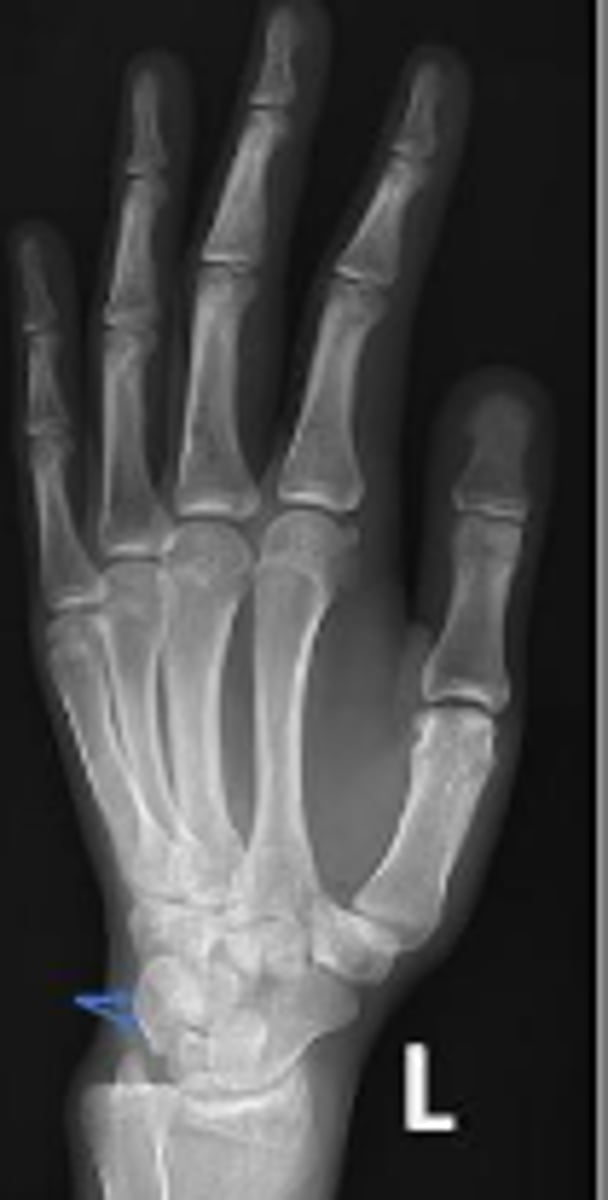

Left lateral wrist

What is the name of the radiographic view?

Left lunate

What is outlined?

Left pisiform

What is the arrow pointing to?

Left capitate